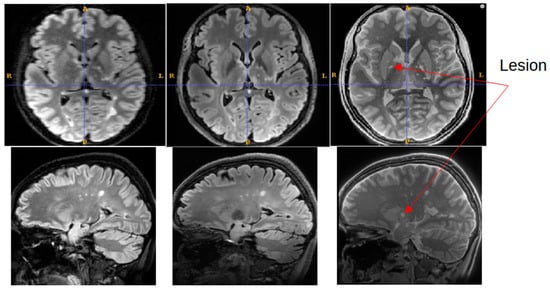

An experienced neuroimaging researcher and two radiologists reviewed the registered 1.5T FLAIR, the registered 7T FLAIR, and the SilentMT images from the MS patient. A consensus was reached among the reviewers that the SilentMT image detected all the same MS lesions as the 1.5T FLAIR. We observed that while 7T FLAIR also detected the MS lesions in most slices, MS lesions were not always detected in the brain-stem and in the temporal lobes.

Examples of lesions not being detected in the temporal lobe are given in Figure 5. In Figure 5, we count 3 lesions in the right temporal lobe (blue circle) which are visible on 1.5T FLAIR (left) and SilentMT (right), but are not apparent on the 7T FLAIR (centre). In the left temporal lobe, we can see 1 lesion on the 1.5T FLAIR and the SilentMT, but the same lesion is not visible on the 7T FLAIR.

Figure 5. 7T FLAIR contrast loss in left temporal lobe. MS lesions are visible (blue circle) on 1.5T FLAIR (left) and SilentMT (right). MS lesions are not visible on 7T FLAIR (centre).

Figure 6 shows a representative slice from the MS patient where an MS lesion detected with SilentMT was not immediately apparent on either FLAIR sequence. The lesion is located peri-ventricularly in a region likely to be clinically relevant for MS but was not initially detected on the FLAIR sequences. Subsequent radiologic review of this region reached the consensus that the lesion was not visible on the 7T FLAIR and was of such faint and blurred appearance on the 1.5T FLAIR that it could easily have been missed in a normal clinical review. The lesion was slightly more conspicuous on the 1.5T sagittal FLAIR image (the original plane of acquisition) than on the axial reformatted 1.5T FLAIR image.

Figure 6. Lesion detected on SilentMT (red arrows) but not observed on axial 1.5T FLAIR or 7T FLAIR. Subsequent radiologic review showed the lesion with a faint and blurred appearance on 1.5T sagittal FLAIR.